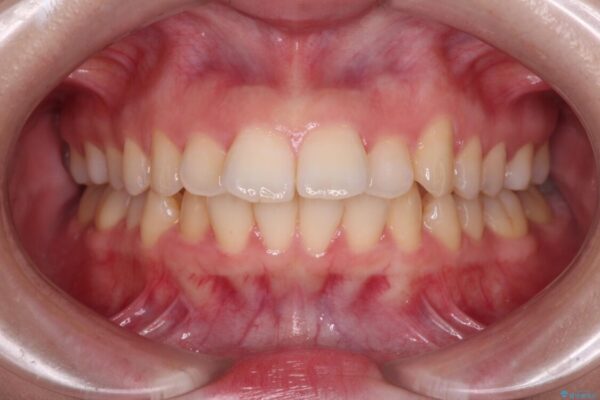

治療後について

舌の突出癖があり、前歯の移動量も多くなるため、治療期間は長くなると予想されましたが、13ヶ月という予定の半分程度の期間で終えることができました。

治療後